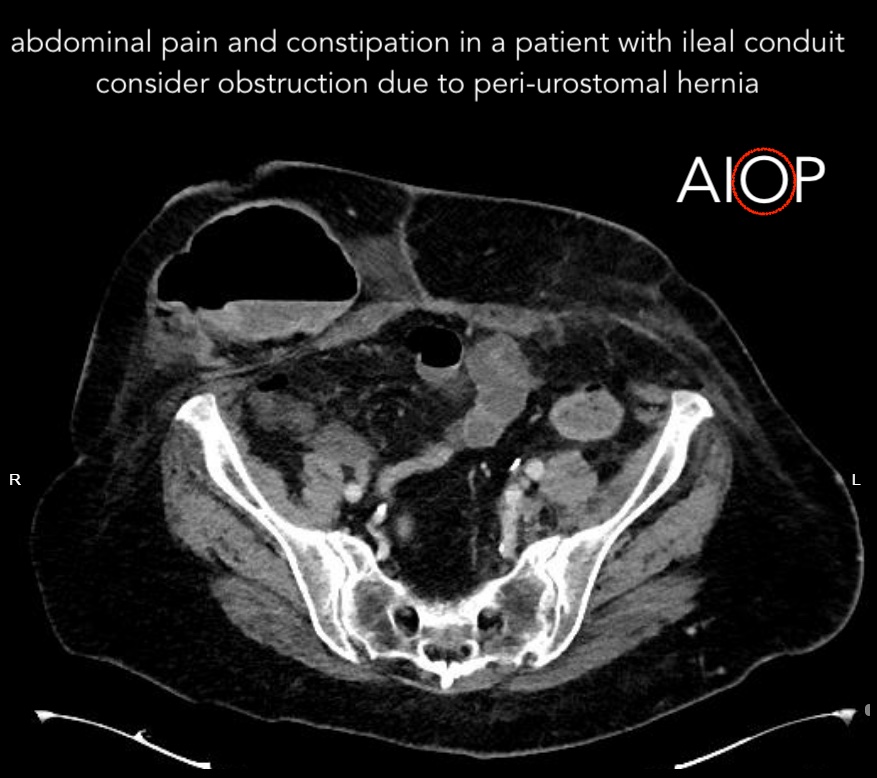

abdominal pain